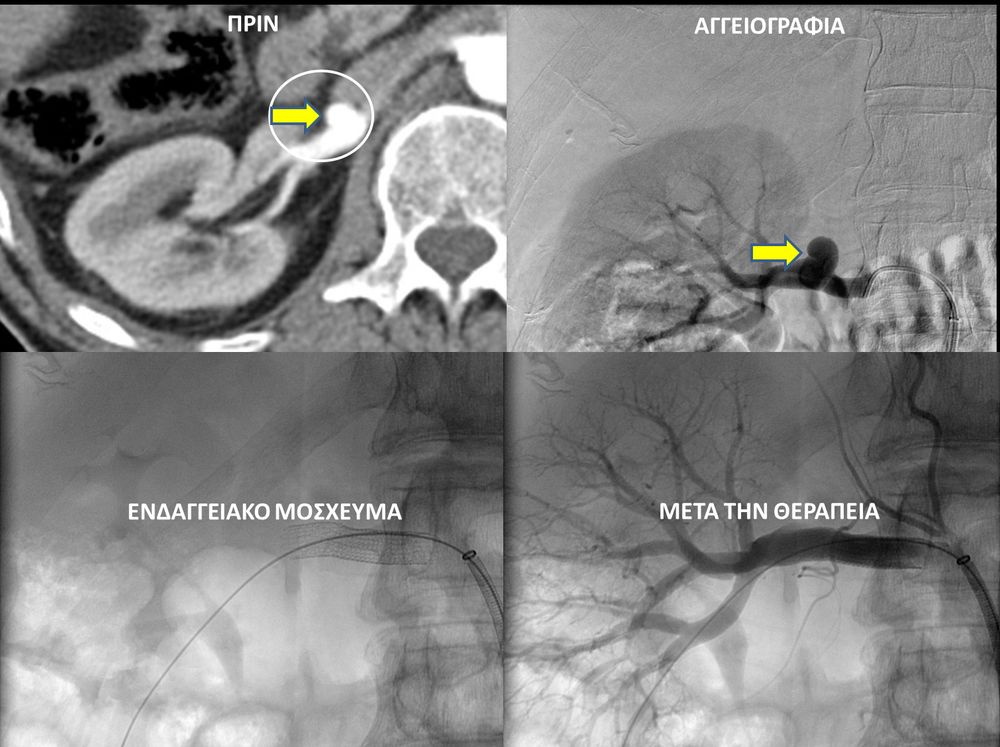

Ο επεμβατικός ακτινολόγος θα προσεγγίσει το παθολογικό αγγείο ενδοαυλικά και με απεικονιστική καθοδήγηση θα τοποθετήσει τακατάλληλα υλικά αποκατάστασης του ανευρύσματος. Υπάρχουν μια σειρά από επιλογές θεραπείας και η θεραπεία, που θα επιλεχθεί, εξαρτάται από την τοποθεσία και το σχήμα του ανευρύσματος.Μία πιθανή επιλογή για ενδαγγειακή θεραπεία περιφερικής αρτηρίας είναι η χρήση ενδαγγειακού μοσχεύματος stent-graft. Εναλλακτικά, το εσωτερικό του ανευρύσματος μπορεί να γεμίσει με εμβολικό υλικό (μικρά σπειράματα-coils ή ειδικη κόλλα), το οποίο εμποδίζει την ροή αίματος στο ανεύρυσμα.